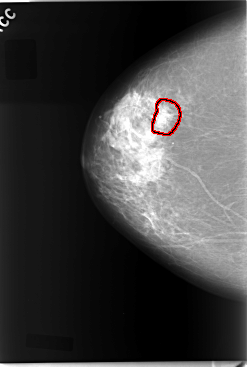

C_0045_1.RIGHT_MLO

RIGHT_CC LINES 5864 PIXELS_PER_LINE 3952 BITS_PER_PIXEL 12 RESOLUTION 50 OVERLAY

FILE: C_0045_1.RIGHT_CC.OVERLAY

TOTAL_ABNORMALITIES 1

ABNORMALITY 1

LESION_TYPE CALCIFICATION TYPE PLEOMORPHIC DISTRIBUTION CLUSTERED

ASSESSMENT 5

SUBTLETY 4

PATHOLOGY MALIGNANT

TOTAL_OUTLINES 1

BOUNDARY